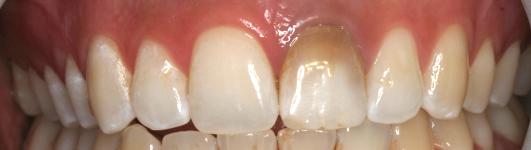

Un ancien traitement de racine est présent sur l'incisive gauche

Il a coloré la base de la dent

Au bout de 2 mois et 4 séances de blanchiment interne